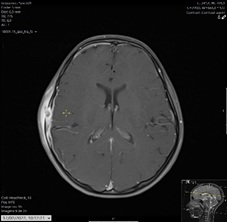

After two days, she had a magnetic resonance imaging (MRI) that confirmed the suspicion of Langerhans cell histiocytosis (LCH) (Figures 3 and 4).

Figure 4: Axial T1-W post-gadolinium show temporal lesion, with adjacent soft tissue involvement.